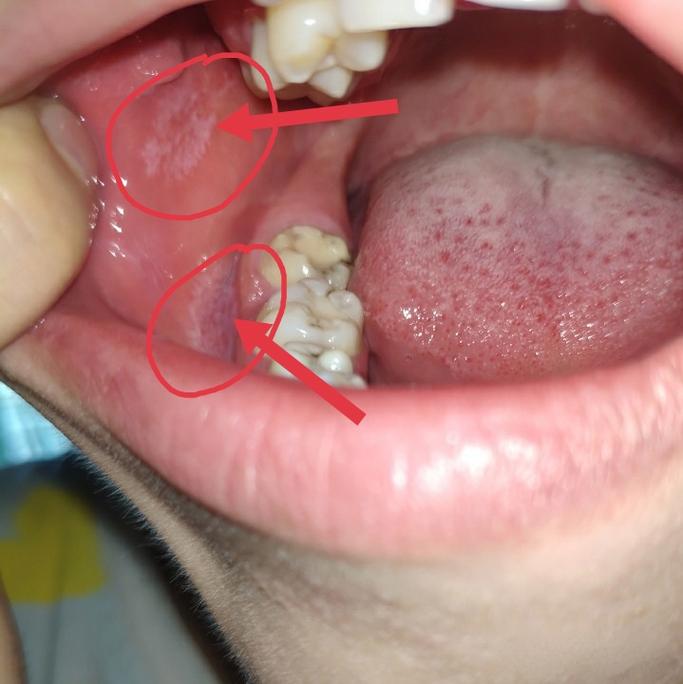

(图片来源网络,侵删)